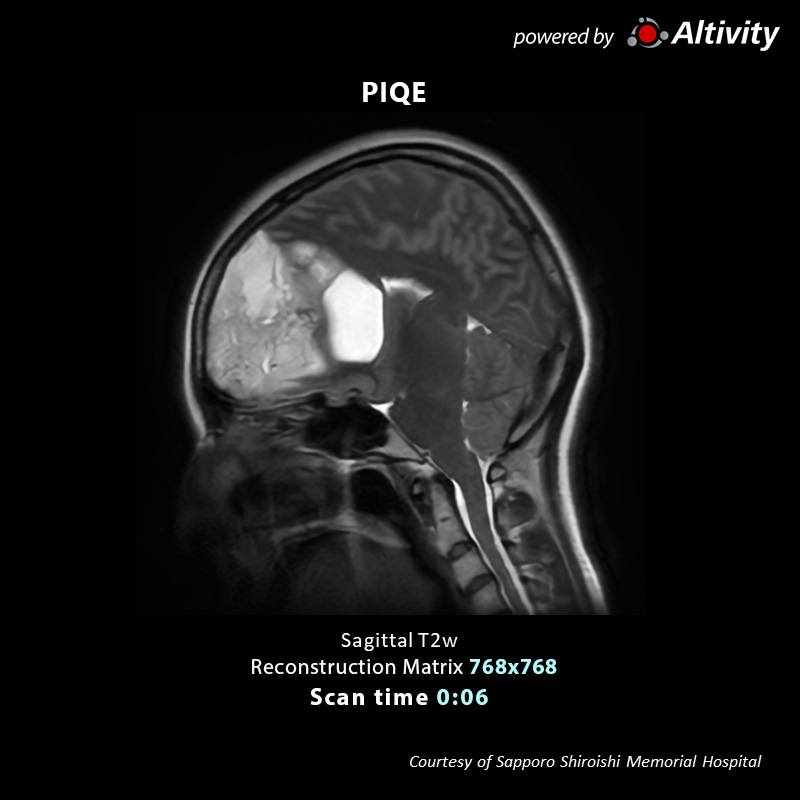

Deep Learning Reconstruction for MR: PIQE

Precise IQ Engine (PIQE)

Accelerate high resolution imaging

PIQE accelerates scanning by reducing the acquisition matrix and enables acquisition of higher resolution images.

Actual scan time and scan time reductions shown throughout this gallery may vary by case.